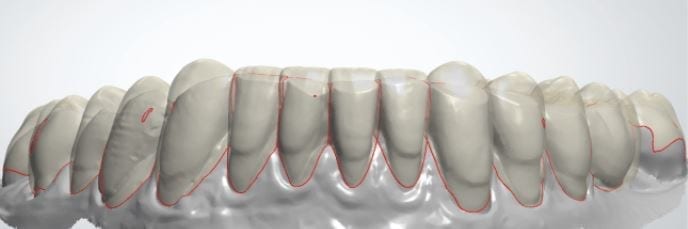

The digital models were then imported into a third party software where a library of tooth morphologies are available for the clinician to choose from.

Once the appropriate library is chosen, the digital wax ups are performed. In the subsequent photos you can see the transparent overlay of the wax-ups to the original position of the existing dentition